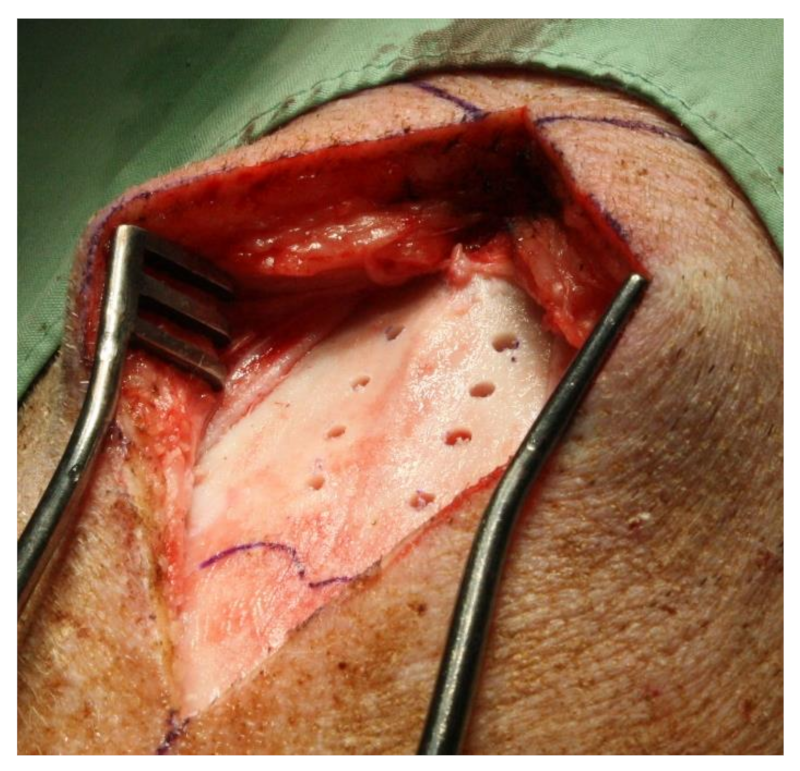

2.1. Surgical Procedure